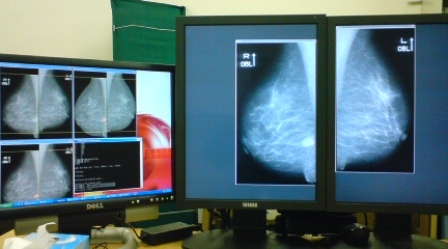

乳房X線画像診断支援システム

女性が最も癌になりやすい乳がんを早期発見するために、医師が診断しやすい画像を自動生成するシステムの開発を行っている。さらに、乳がんの診断所見である腫瘤陰影を自動検出するアルゴリズムに関しても研究を進めている。

mammo.jpg

(左)一般向けカラー液晶モニタによる画像表示 (右)医療用高輝度液晶モニタによる表示